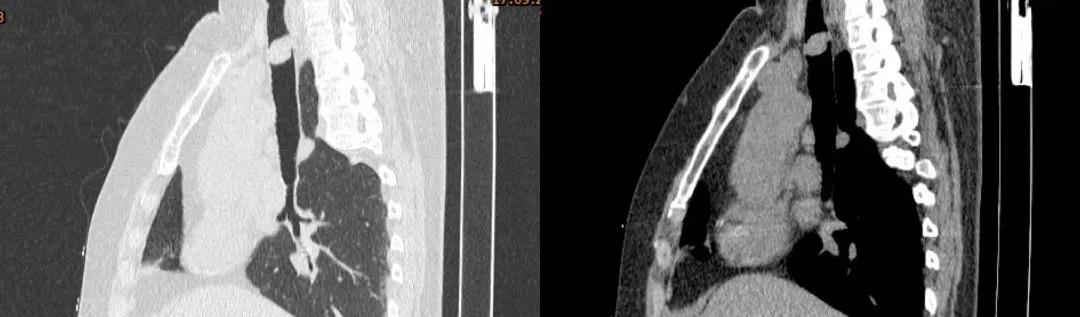

胸部CT:

胸部CT(矢状位)

四、影像学检查:表现为气管腔内的软组织密度肿块